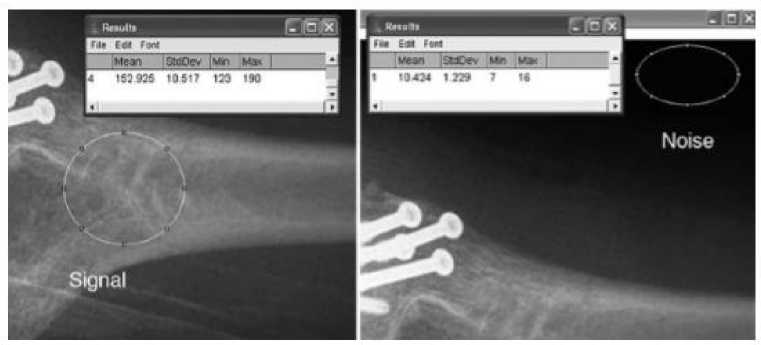

Salah satu parameter kualitas citra digital pada Computed Radiography (CR) adalah Signal to Noise Ratio. Parameter ini menggambarkan tingkat perbedaan antara sinyal yang diukur dengan noise yang juga masuk dalam hasil pengukuran. Semakin besar nilai SNR, maka sinyal dan noise semakin mudah dibedakan. Nilai SNR dapat dihitung dengan menggunakan persamaan (1) [5] serta letak noise dan sinyal pada citra ditunjukkan pada Gambar 1.

SNR = 1)

Is adalah nilai rata-rata sinyal yang diterima oleh imaging plate dan σb adalah nilai simpangan baku dari daerah noise (background).

Gambar 1. Letak noise dan sinyal pada citra [10].

X (kV) sebesar 40 kV, arus sebesar 100 mA dan waktu sebesar 0,05 detik. Selanjutnya dilakukan eksposi atau penyinaran. Kaset CR yang telah di eksposi dilakukan proses image reader oleh scanner sehingga hasil citra akan muncul pada layar monitor CR. Langkah ini dilakukan kembali dengan variasi tegangan lainnya yaitu 50, 60, 70, 80, dan 90 kV. Hasil citra kemudian dilakukan pembacaan nilai Is, dan σb menggunakan software program RadiAnt DICOM VIEWER 2020.1 sesuai dengan ROI (Region of Interest) yang telah ditentukan pada masing-masing ketebalan stepwedge. Luas ROI yang digunakan sebesar 0,241 cm2. Pembacaan nilai pada ROI dilakukan dengan 3 kali pengulangan, ditunjukkan pada Gambar 3. Dari nilai Is dan σb kemudian dilakukan perhitungan untuk menentukan nilai SNR. Selanjutnya dilakukan analisis data pengaruh variasi tegangan sinar-X terhadap perubahan nilai SNR.

Gambar 3. Proses pembacaan nilai Is, Ib, dan σb.